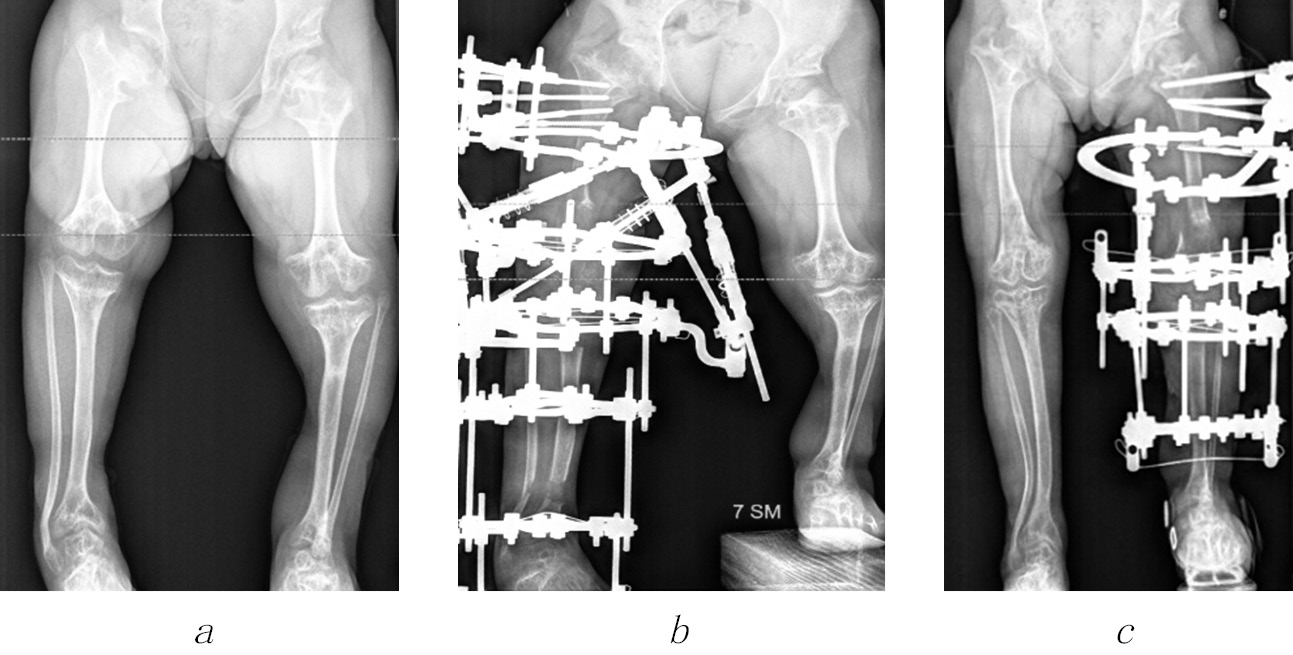

In our series of cases, in 8 out of 12 (66.7%) patients, we noted lesion to the proximal growth zones of the femoral bone with the formation of varus deformities of the necks, which necessitated surgical correction (Fig. 4).

Fig. 4. Radiographs of the hip joints of patients K. (a) and A. (b) with varus deformities of the femoral necks